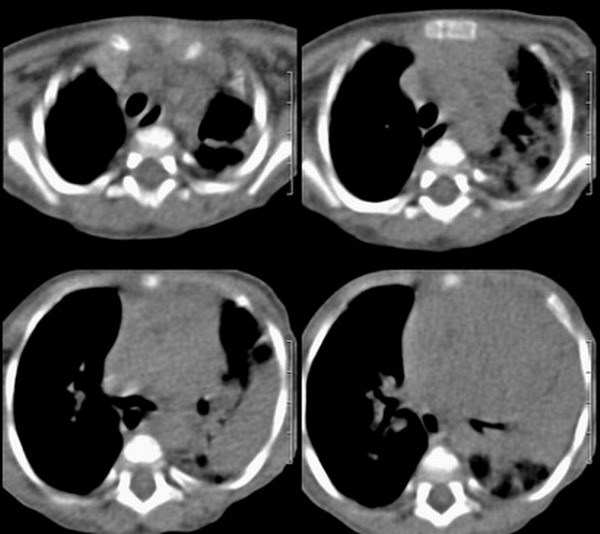

患儿 六月 咳嗽,反复发热二周,加重伴气喘3天

左肺呈大片状实变影,密度欠均匀,边界模糊,残存正常的肺组织呈气肿表现,右肺内可见磨玻璃样改变,如此年幼的婴儿首先考虑左肺发育不良并继发感染可能性大

左肺呈大片状实变影,密度欠均匀,边界模糊,残存正常的肺组织呈气肿表现,右肺内可见磨玻璃样改变,考虑左肺发育不良并继发感染可能性大.图象太小

此患儿于前日死亡,病检结果:

左肺发育不良伴感染.